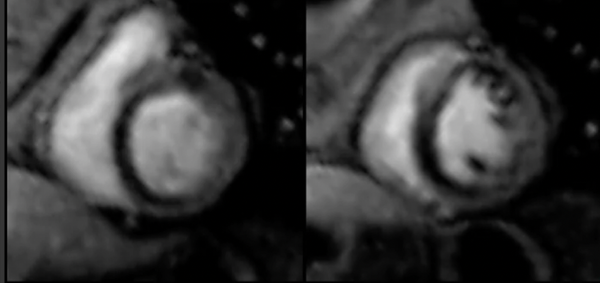

Infarcts

Ischaemic HD

Adenosine stress perfusion CMR is a powerful tool to predict present and future events